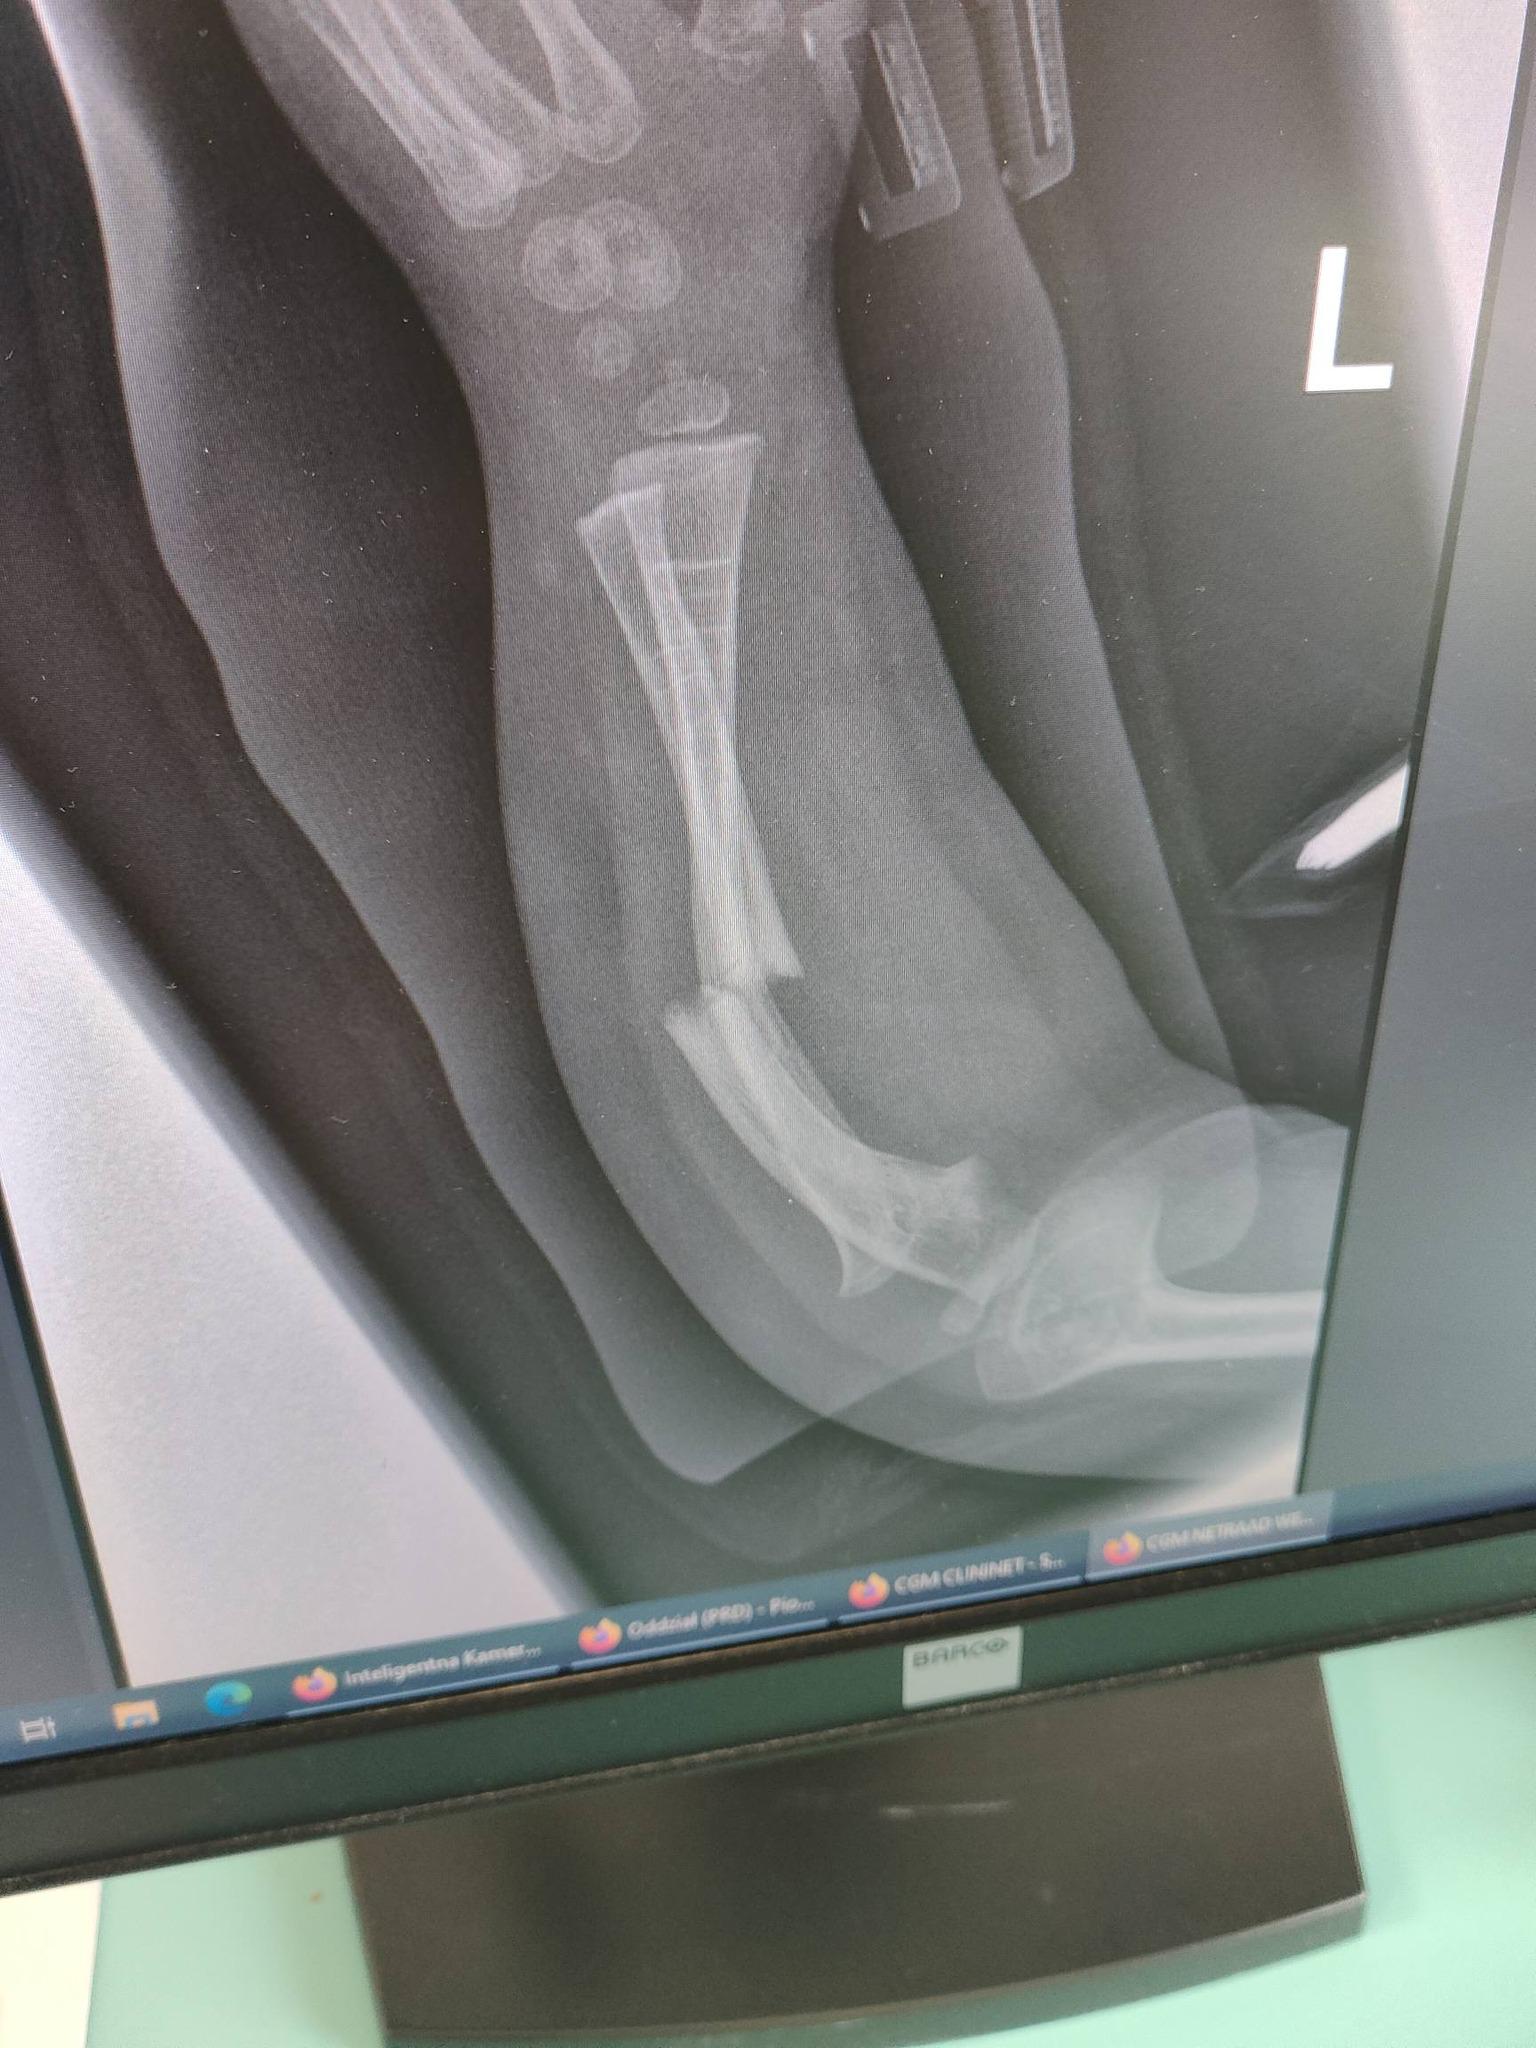

Madzia choruje na wrodzoną łamliwość kości typu III (osteogenesis imperfecta) – rzadką, genetyczną chorobę tkanki łącznej, która powoduje skrajną kruchość kości. Złamań doznała już w życiu płodowym, a jej organizm nie produkuje kolagenu. Choroba jest nieuleczalna, a leczenie ma charakter objawowy i obejmuje stałą rehabilitację, liczne operacje, stabilizację kości oraz specjalistyczną farmakoterapię. Dziewczynka ma za sobą już kilka poważnych zabiegów oraz kilkanaście podań leków wzmacniających kości. Przed nią kolejne operacje i intensywna fizjoterapia, bez której trudno byłoby myśleć o większej samodzielności.